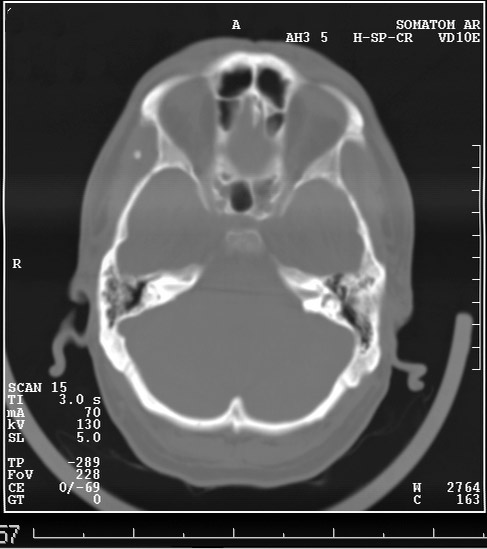

Выкладываю данные КТ

На снимке утолщение веретенообразное мышечного слоя с наличием кальцификатов(два) Кальцификаты в мышце чаще встречаются при паразитарных инфекциях(трихиниллез,токсоплазмоз,цистецеркоз),но их больше по количеству и в разных местах.Оссифицирующий миозит-имеет свою картину и распространение.Насчет Хортона-навряд ли,это же поражение сосуда.Насчет тофусов-они содержат ураты,чаще локализуются подкожно(не в мышце),при подагре осификации вдоль сухожилий.А может был удар,гематома с частичной кальцификацией?